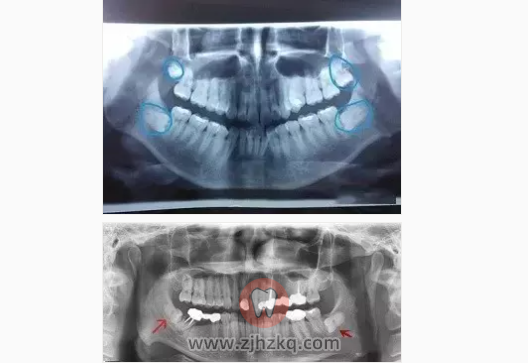

智齿:是口腔最靠近喉咙的牙齿,从正中的门牙往里数刚好是第八颗牙齿,通常情况下应该有上下左右对称的4颗牙。由于它萌出时间很晚,一般在16~25岁间萌出,此时人的生理、心理发育都接近成熟,有“智慧到来”的象征,因此被俗称为“智齿”。

在已萌智齿中阻生和错位约占44% ,

其中发生在下颌者约是上颌者的2.5倍。

在X线片上可以看得很清晰。